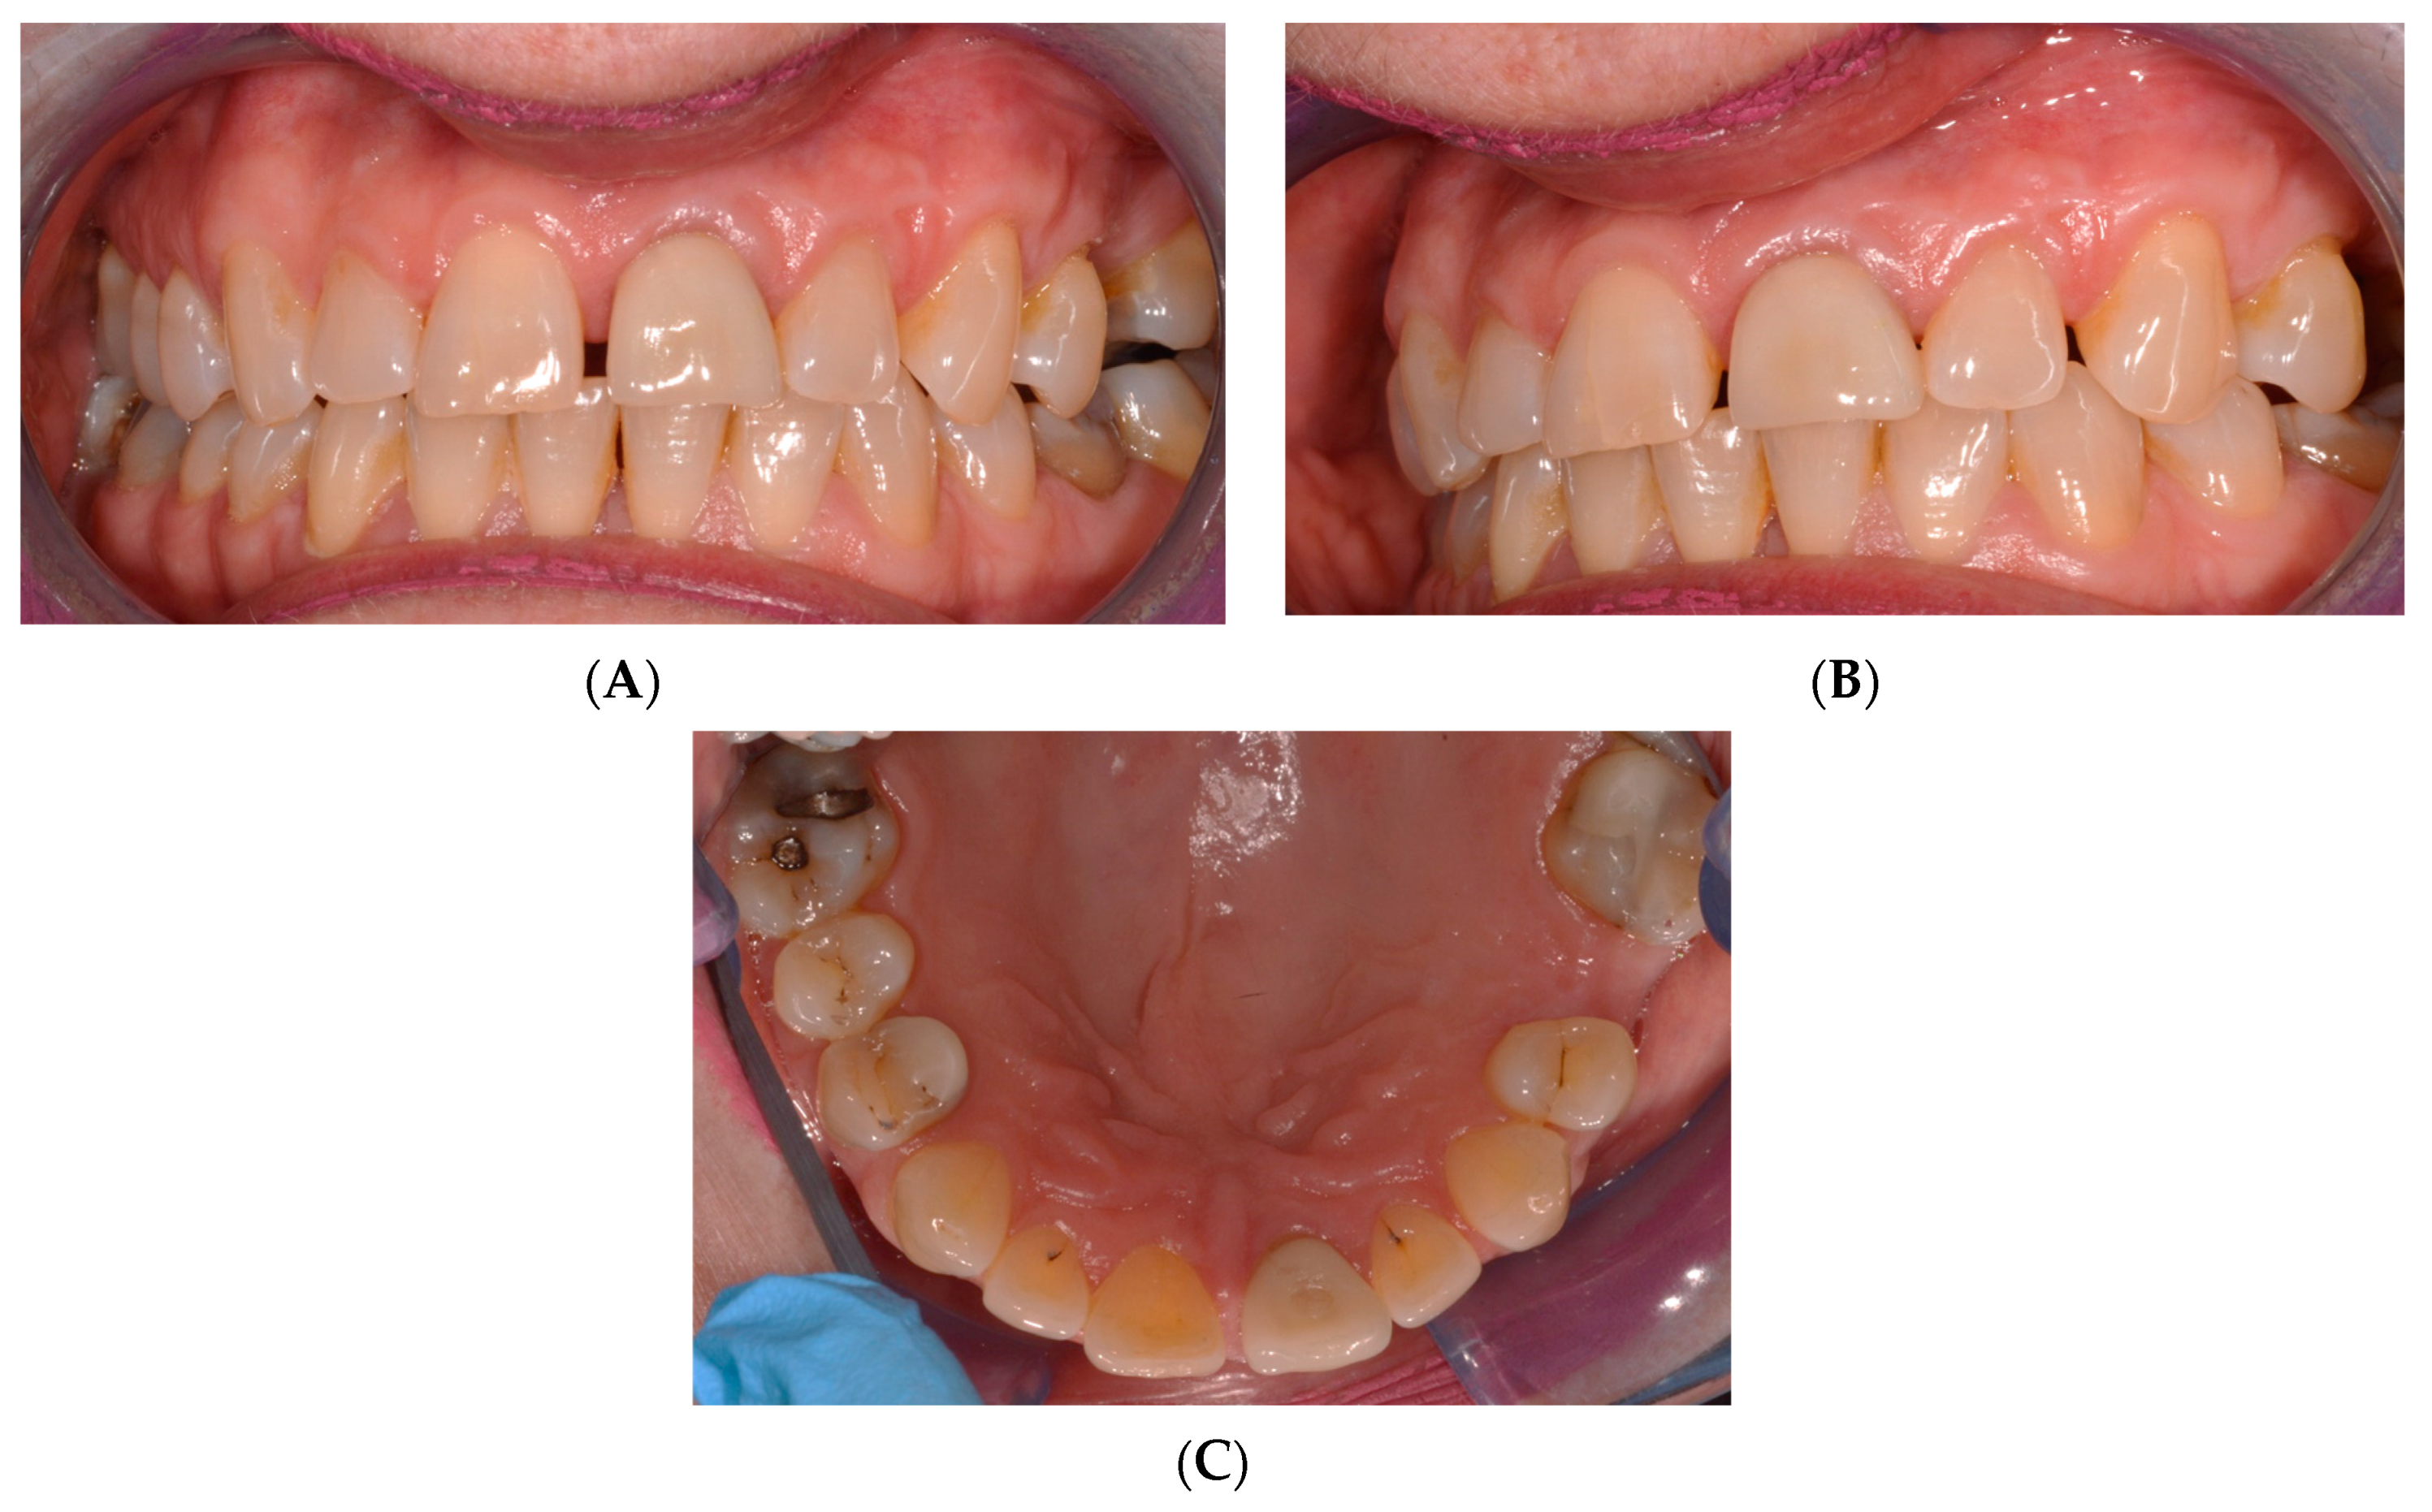

2. Case Presentation

2.1. Chief Complaints History and Clinical Findings

2.2. Delivery of Treatment

2.4. Healing of the Defect and Follow Up